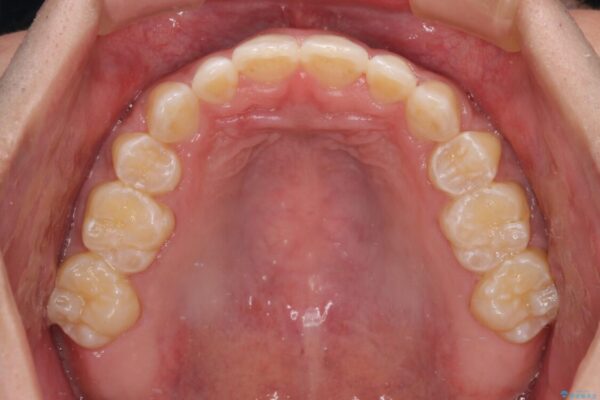

受け口傾向特有の狭い上顎歯列であったため、歯列の拡大を補助装置で行い、下顎歯列全体を後方に移動させることとしました。

奥歯の咬み合わせを改善させた後、上下左右の小臼歯(下顎は残存乳歯)を計4本抜歯し、ワイヤー装置にて口元の突出感を改善しながら咬み合わせを整えることとしました。

治療前

• 口元の突出感を改善 受け口傾向の咬み合わせの抜歯矯正 治療前画像